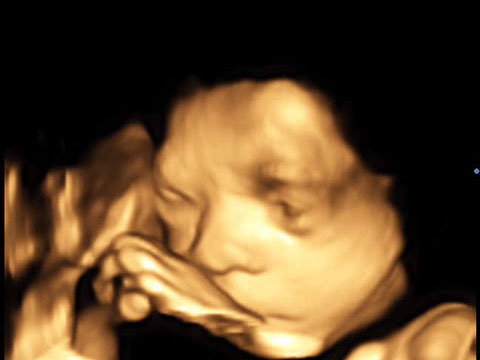

4D-Ultraschall

Der 4D-Ultraschall ist eine Methode der Ultraschall-Untersuchung, bei der das Ultraschallgerät ein dreidimensionales Bild des Untersuchungsobjekts in Echtzeit erzeugt.

Hier zeigt ein kleiner Film einen 4D-Ultraschall